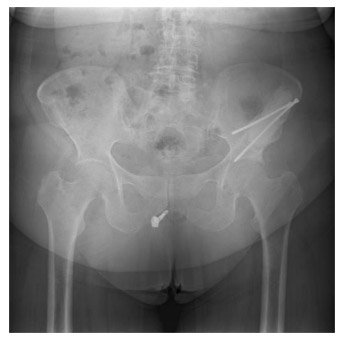

Postoperative: The X-ray shows that after the tumor was removed, the resulting cavity was filled with bone cement and reinforced with two long screws.